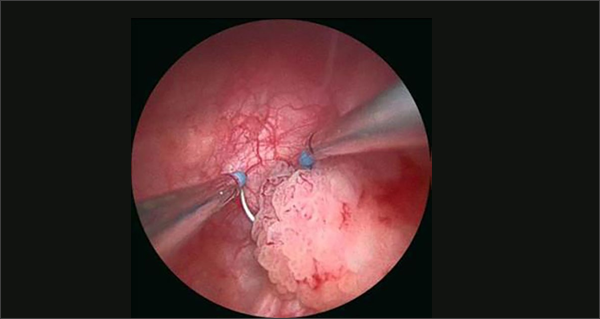

CYSTOSCOPIC VIEW OF BLADDER TUMOR

TUR OF BLADDER TUMOR